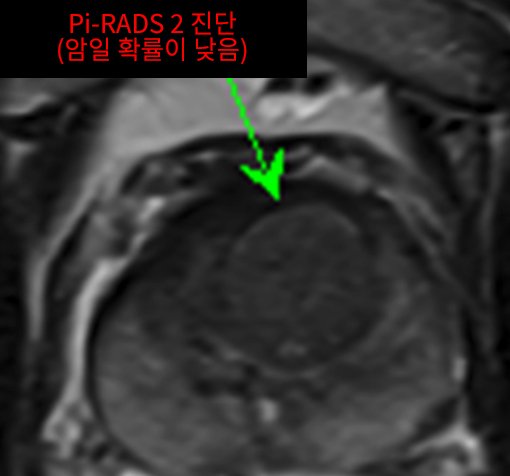

Case of treatment

아미랑에서 치료하신 분들의 소중한 치료사례를 담았습니다.